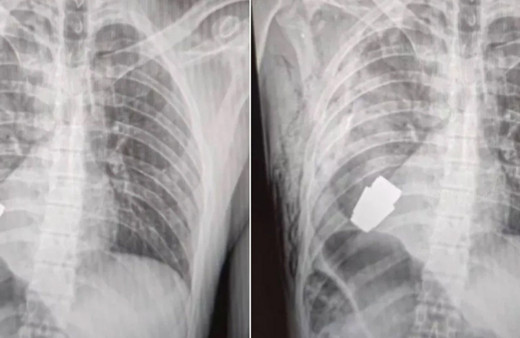

Ukrayna